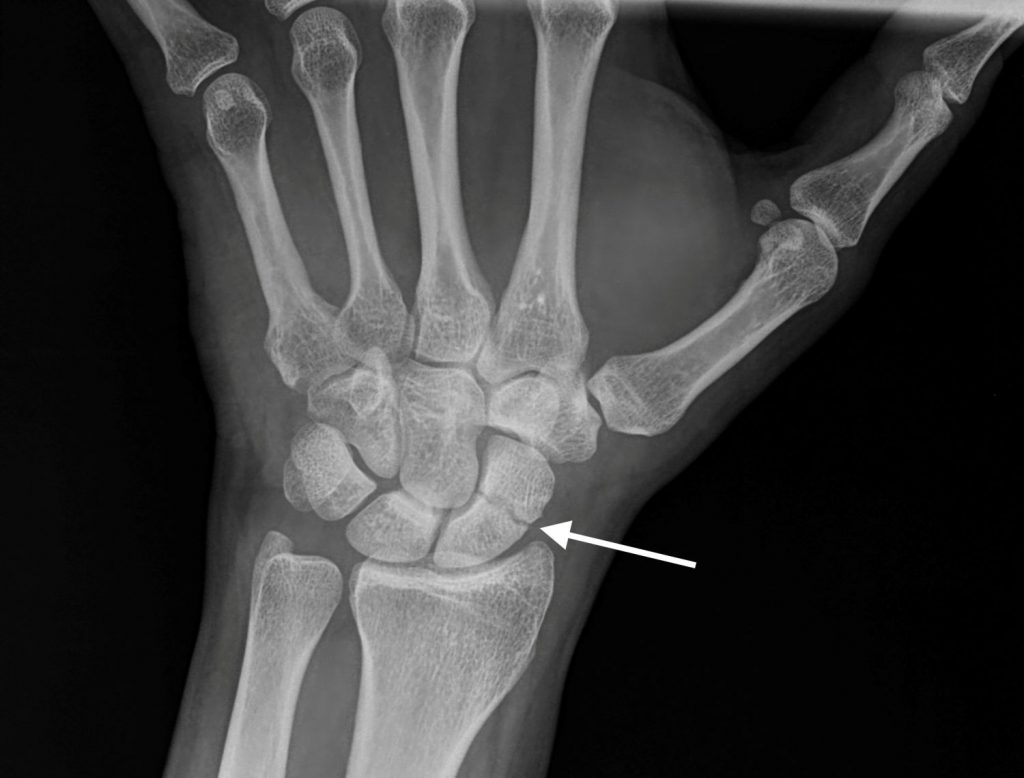

Es fundamental una exploración física minuciosa y unas correctas radiografías para poder realizar el diagnóstico que, aún así, puede ser difícil de establecer de inicio (Figura 2).  En algunos casos serán necesarias, además, otras pruebas de imagen como TAC y/o Resonancia Magnética para el diagnóstico definitivo.

Figura 2 - Radiografía simple muestra fractura de escafoides.